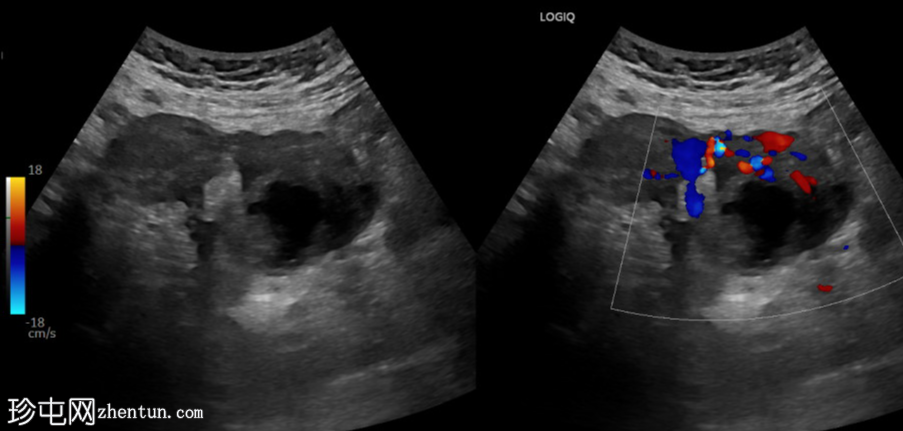

超声检查

斜切面

左侧卵巢明显增大,可见一囊肿,大小约3.2 x 2.3 cm,呈火环征,可能为黄体囊肿。左侧卵巢与子宫之间可见一管状结构,直径约1.3 cm,内含浑浊液体,未见血管,最可能为输卵管积血。以上特征提示可能为左侧异位妊娠。

未见宫内妊娠囊。